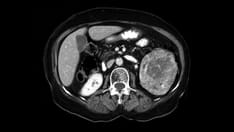

The presentation, evaluation, and diagnosis of AA are notoriously inconsistent; many factors attribute to these discrepancies. The classic history consists of anorexia and periumbilical pain, followed by nausea, right-lower-quadrant (RLQ) pain, and vomiting, as well as leukocytosis. [2] History and physical examination should provide enough clinical information to diagnose AA, with the use of imaging modalities as adjuncts in the assessment.